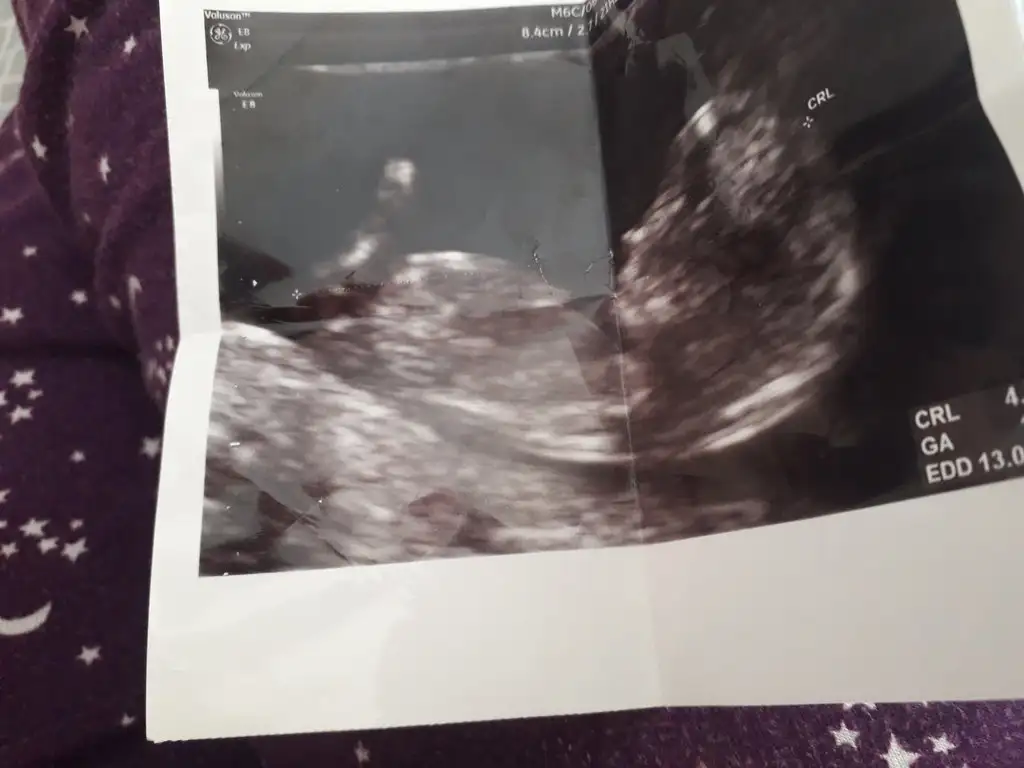

Kafasi kare gibi sanki erkek ama goruntuyu yakinlastirmamis doktor emin olamadim

Ben erkek diyorum cunku cenesi belirgin degil ve alni duz

Hemen ultrason fotosuna baktim benimki kiz o zaman. Cenesi burnu cok dikkatimi cekmisti zaten kontrolde de sivri ve cok muntazamdiBende burda bi konudan ogrendim kizlarin kafalari daha narin ceneleri sivri oluyormus erkeklerin kare oluyormus kafasi skull teorisi mi ne konunun adı

Benimkinin de kafasi kare :) nubu kiz gibi gelmisti ama sonradan farkettim hafif arkasi donukmusHemen ultrason fotosuna baktim benimki kiz o zaman. Cenesi burnu cok dikkatimi cekmisti zaten kontrolde de sivri ve cok muntazamdibelki de bir erkek guzei geliyordur